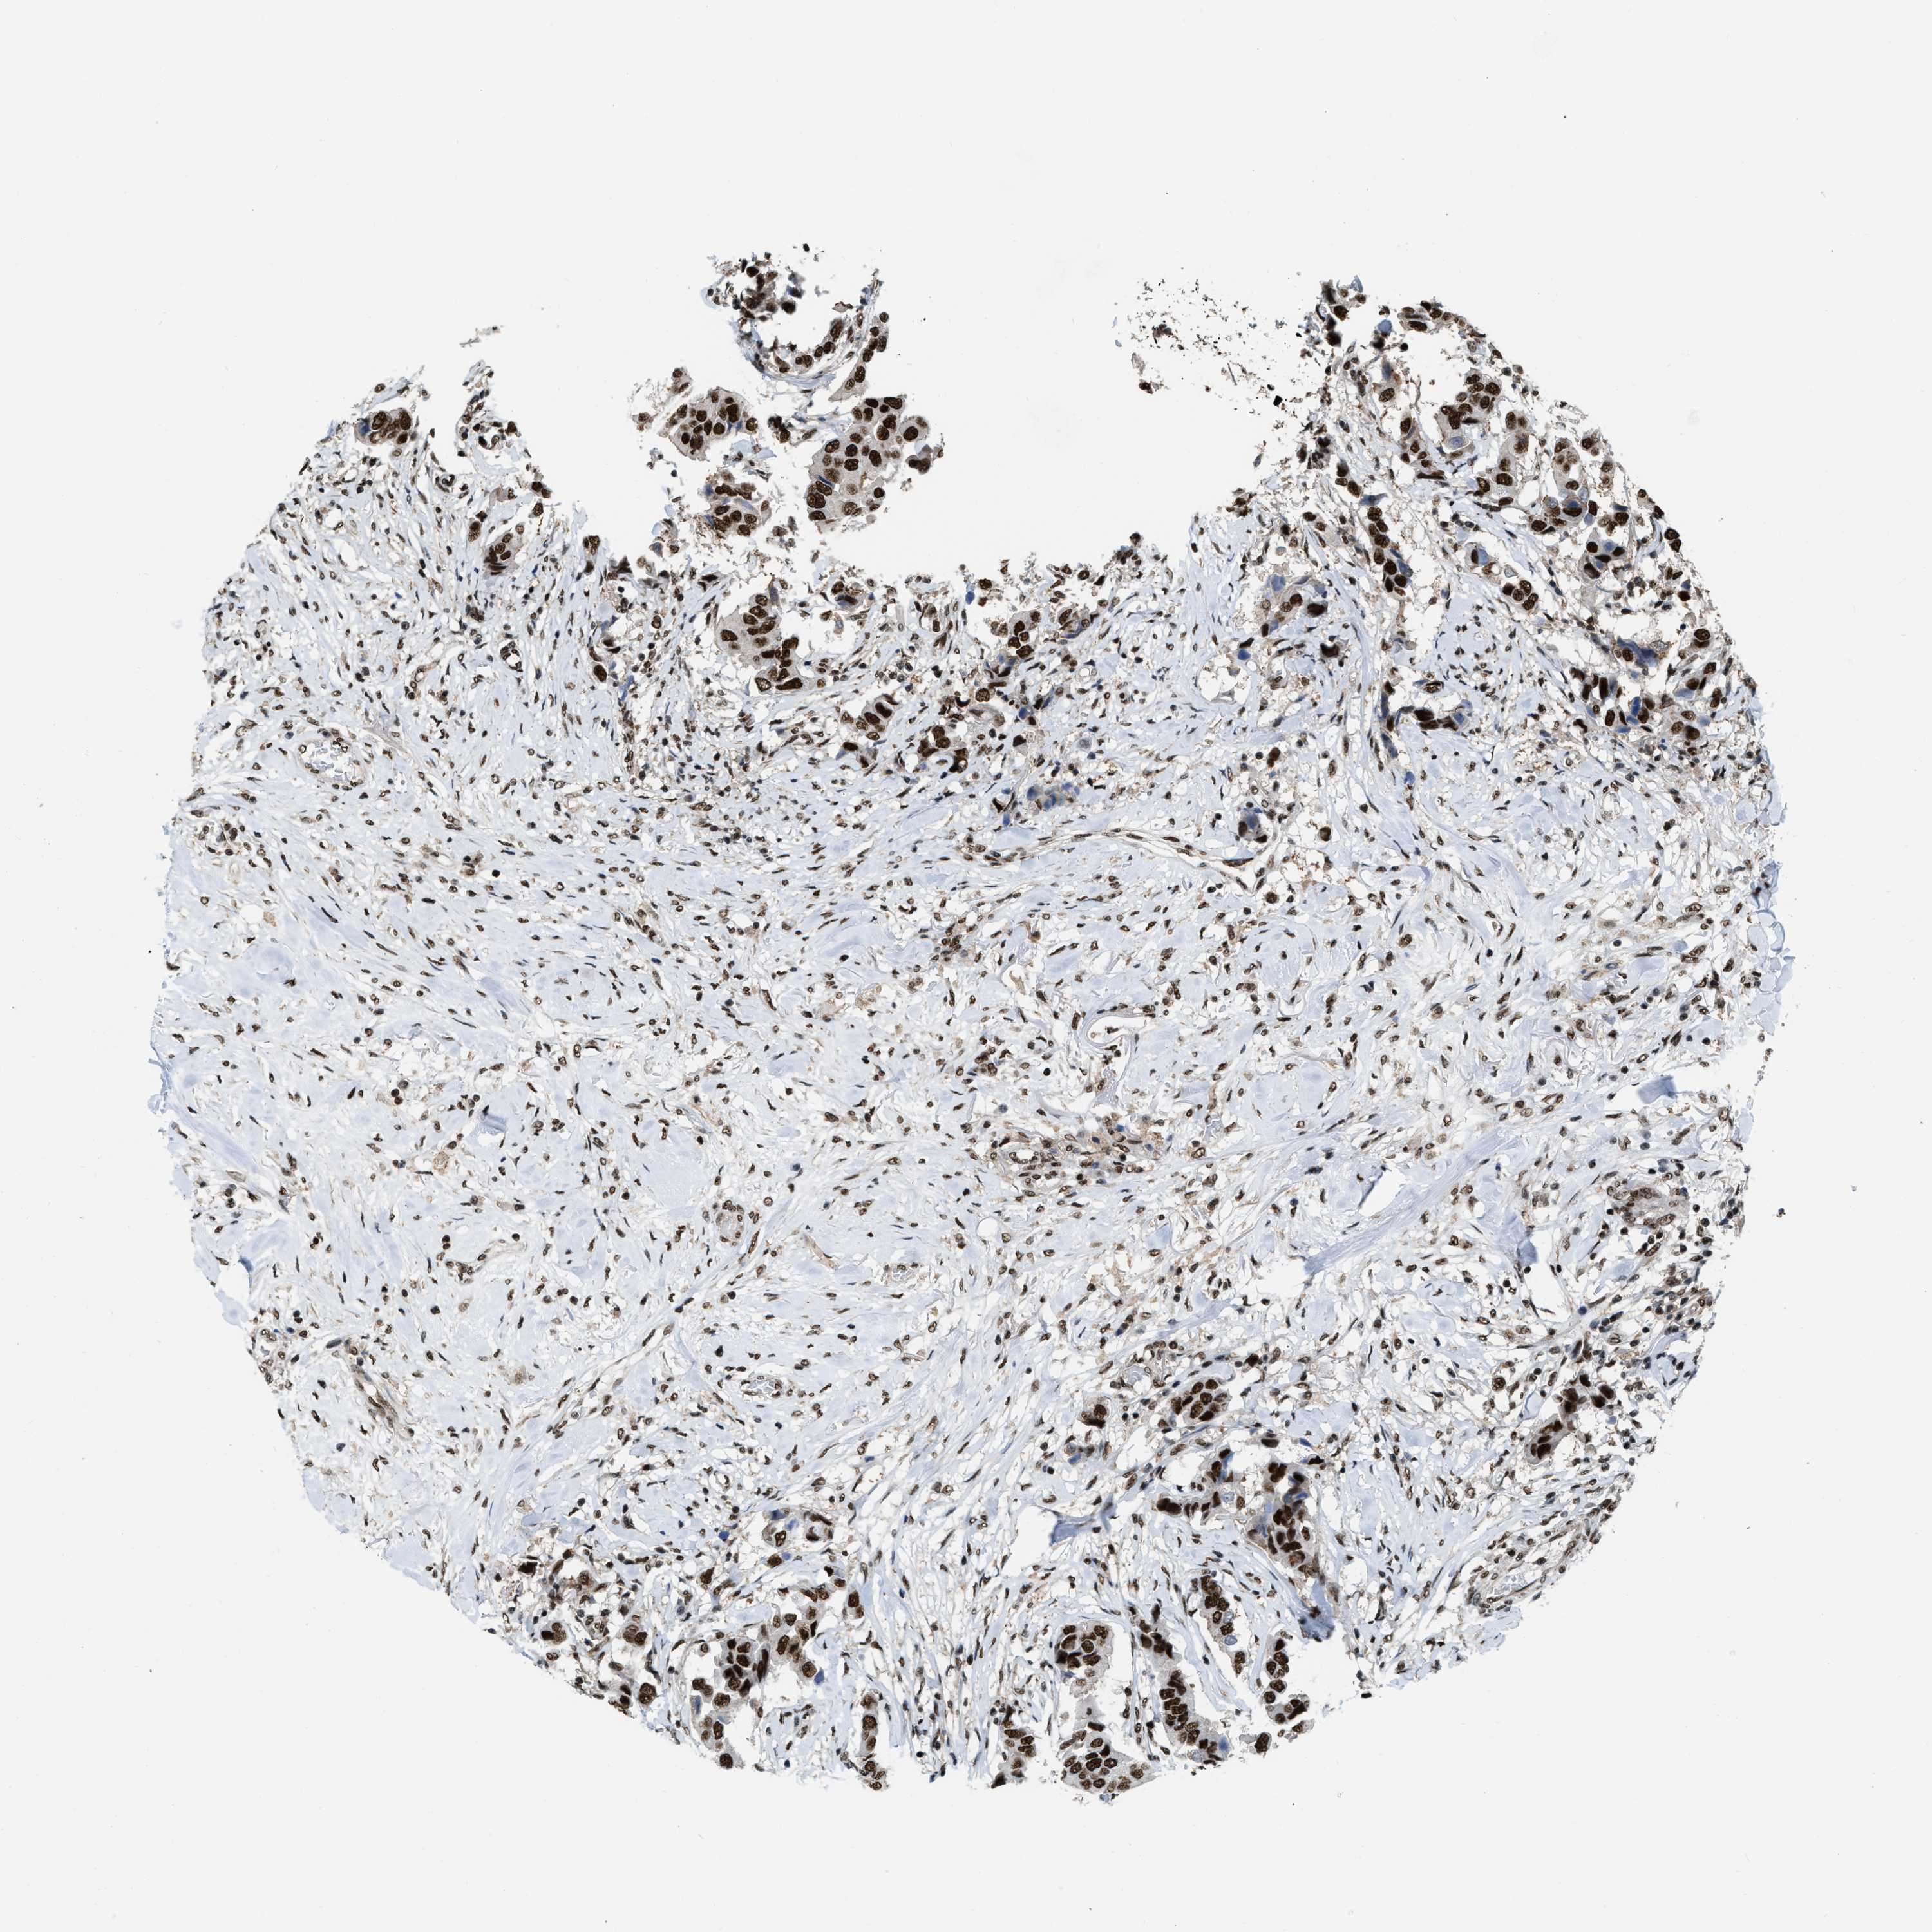

CANCER BREAST CANCER Show tissue menu

BRCA TCGA BRCA VALIDATION PROTEIN EXPRESSION